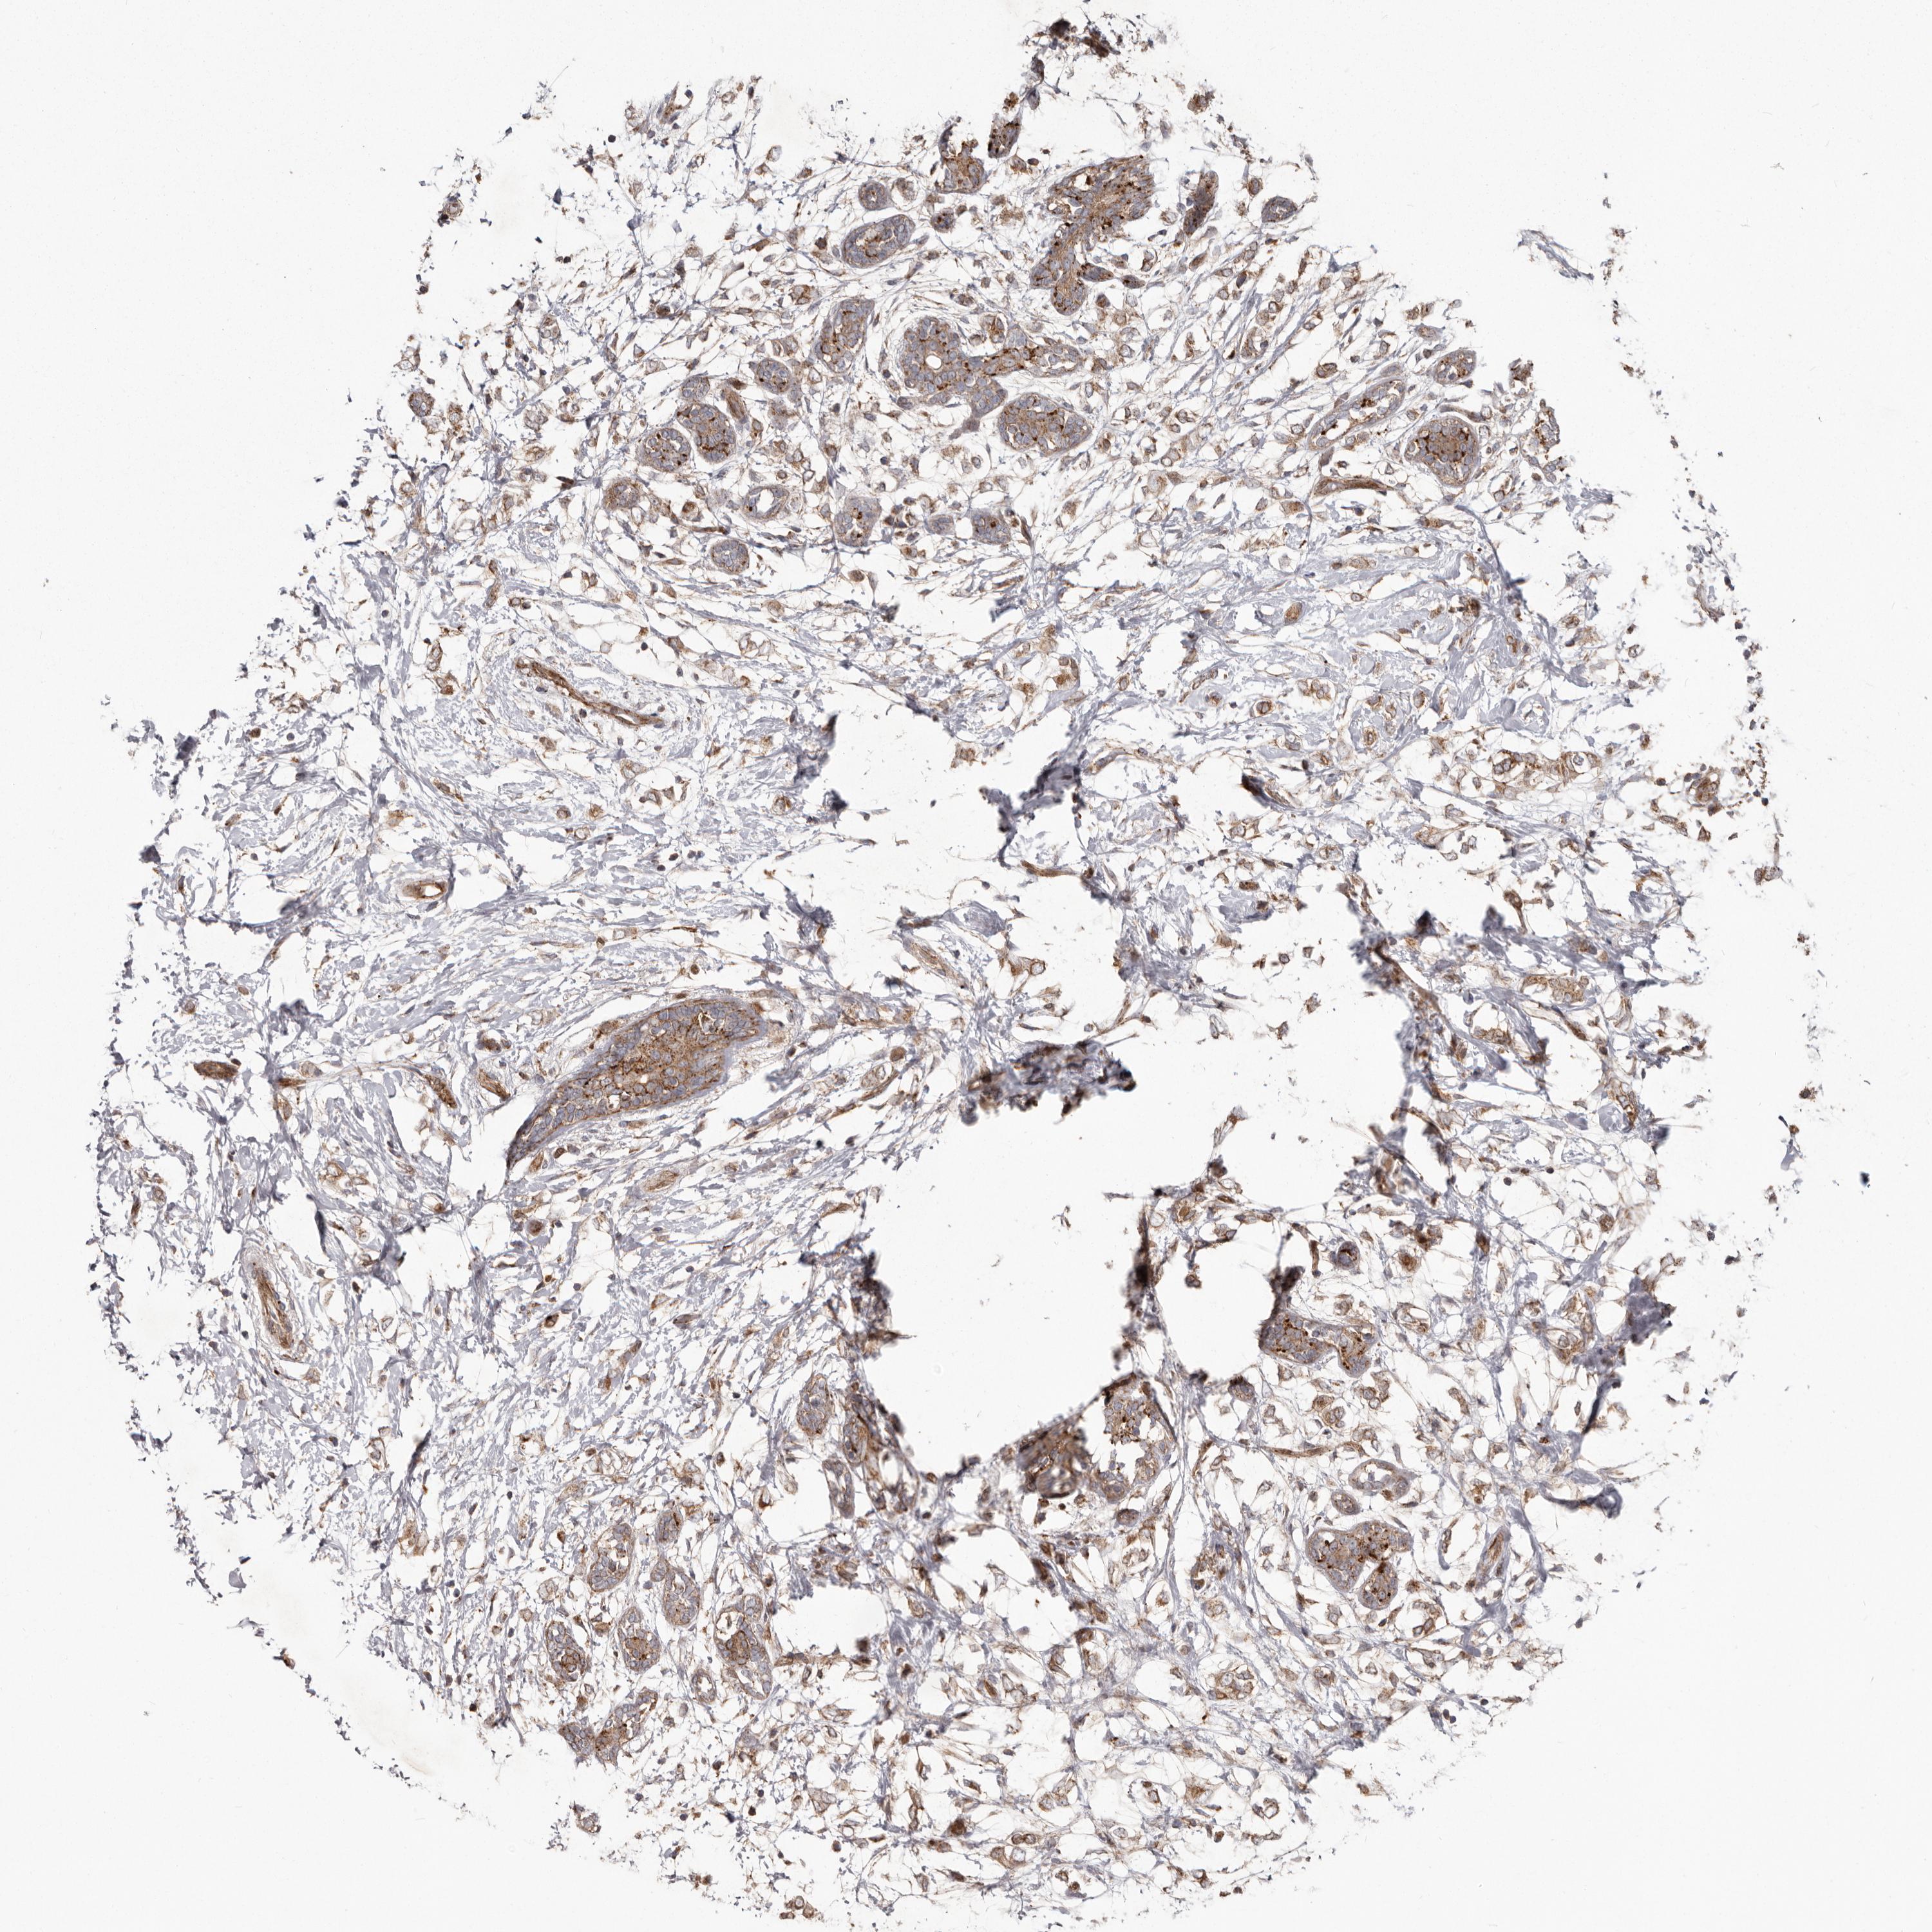

CANCER BREAST CANCER Show tissue menu

BRCA TCGA BRCA VALIDATION PROTEIN EXPRESSION